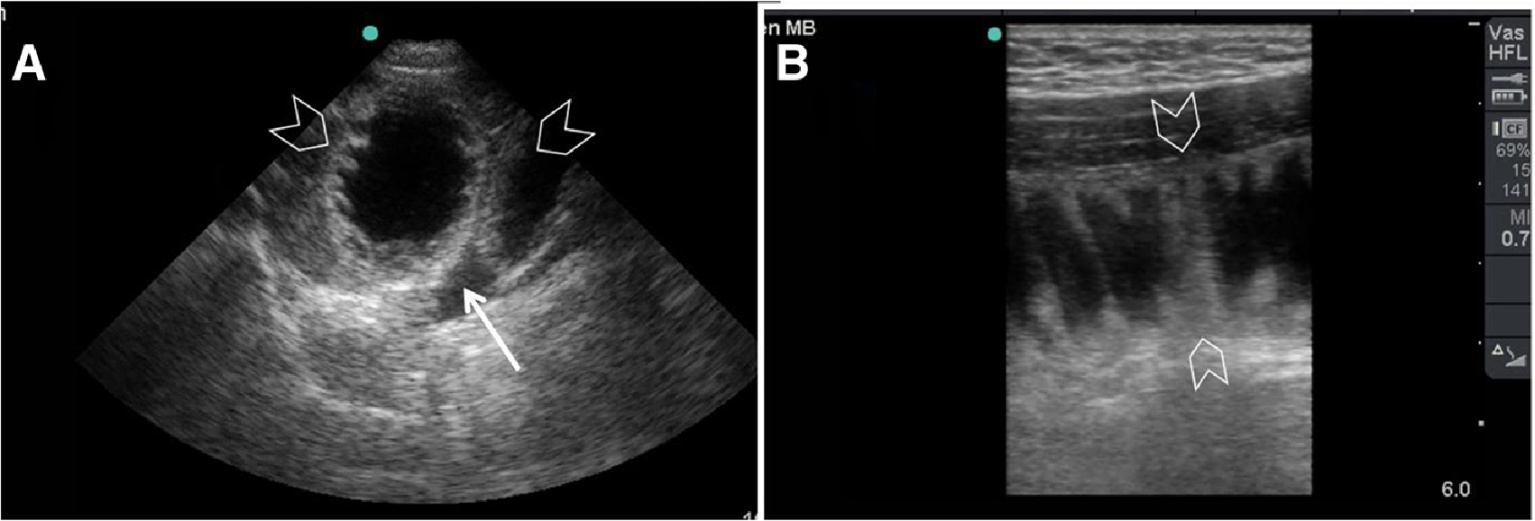

Figure 1. Ultrasound images of hemorrhagic cholecystitis. (A) POCUS demonstrates that the gallbladder lumen is filled with mixed-echo material (arrow), indicative of blood. (B) Color Doppler ultrasound of the gallbladder shows avascularity of the gallbladder wall, with echoic material visualized within the gallbladder lumen

1. 血性胆囊炎超声图。(A) POCUS显示胆囊腔内充满混合回声物质(箭头),代表血液。(B) 胆囊彩色多普勒超声显示胆囊壁缺乏血管,胆囊腔内可见回声物质